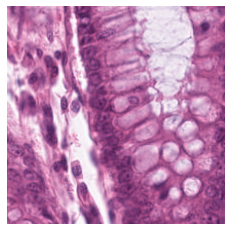

We also analyse the activation maps for each model using GradCAM as described in section S3. This offers more insight into the areas of the image which are contributing most heavily to the models’ representations. In Figure 4(b) we present some representative examples, however, a larger selection which was chosen at random is presented in Figures S10 to S25. The larger selection makes it easier to see the emergent patterns, including that privileged Siamese models tend to mainly identify features which are strongly present in both inputs, while unprivileged Siamese models tend to learn more diffuse features that are not specific to one cell phenotype or image region. TriDeNT ♆ incorporates both sets of features, learning both features specific to the privileged data and more the general features associated with unprivileged Siamese networks.

We can see in Figure 4(b) panel A that for ERG, the privileged Siamese model focuses almost exclusively on any nuclei which could be endothelial cells. As there are very few endothelial cells in the dataset, it could be an effective strategy to identify anything that could potentially be an endothelial cell to minimise the difference between the representations of the H&E model and the IF mask model. In the corresponding unprivileged Siamese image, we see that the model identifies some of these nuclei, albeit less strongly, but also focuses heavily on the other tissue and even the background, while strongly fixating on two spots of debris in the center of the image. This model has less ‘incentive’ to learn the weak features related to endothelial cells as these occur rarely and are not easy to detect, while more generic strong features such as the presence of connective tissue and the prevalence of background are more common and predictable from augmented images. We see that TriDeNT ♆ combines these two feature sets, strongly identifying nuclei while also identifying the connective tissue.

In panel C we see a similar pattern, with the privileged Siamese model fixating solely on the nuclei, while the TriDeNT ♆ model takes a more balanced approach. The unprivileged Siamese model appears to focus on a single cluster of nuclei while neglecting others, and similarly identifies an area of fibroblasts with its distinctive pattern but does not others.

In contrast to panels A and C which represent models with poor privileged Siamese results, panels B and D represent models whose privileged Siamese results were comparable to both TriDeNT ♆ and even the supervised baseline. It is therefore interesting to note that there are far more similarities between the privileged Siamese and TriDeNT ♆ models in both cases. Particularly in panel B, TriDeNT ♆ and the privileged Siamese model return virtually identical heatmaps, with both strongly identifying epithelial nuclei and neglecting the same areas of connective tissue. The unprivileged model in this case appears to focus solely on the centre of the image, giving a significantly different heatmap to the other panels.

Panel D again shows the previous pattern, with the privileged Siamese model identifying the features strongly present in the privileged data – fibroblasts – while neglecting the nuclei present. TriDeNT ♆ also strongly identifies the connective tissue, but, unlike the privileged Siamese model, does not completely neglect the nuclei. The unprivileged Siamese model primarily identifies background, and does not appear to identify the nuclei in this example.